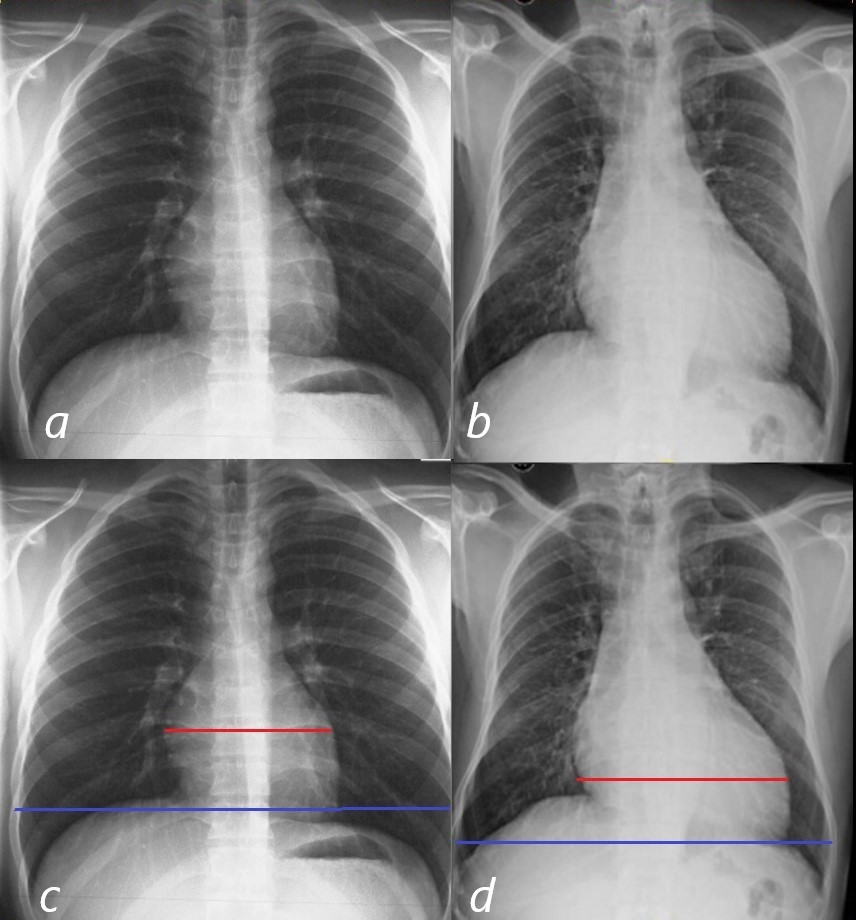

17. NYHA 기준 3단계, 4단계(가장 나쁨)의 중증 심부전 환자 1,663명을 대상으로 기존의 치료 방식대로 혈압약인 ACE 억제제와 이뇨제만 쓴 그룹과, 알닥톤 25mg을 추가한 그룹 간의 치료 경과를 비교했더니 2년 간 추적과정에서 전체 사망률이 무려 30%나 감소하고 (284명, 35% 대 386명. 46%), 심부전으로 인한 입원이 35%가 감소될 정도로 효과가 뛰어났기 때문입니다. (1999년, RALES 연구) 이 연구 역시 이런 효과를 알고도 알닥톤을 심부전 환자에게 주지 않는 것은 윤리적으로 문제가 있다 해서 중도에 종료됩니다.

RALES.png